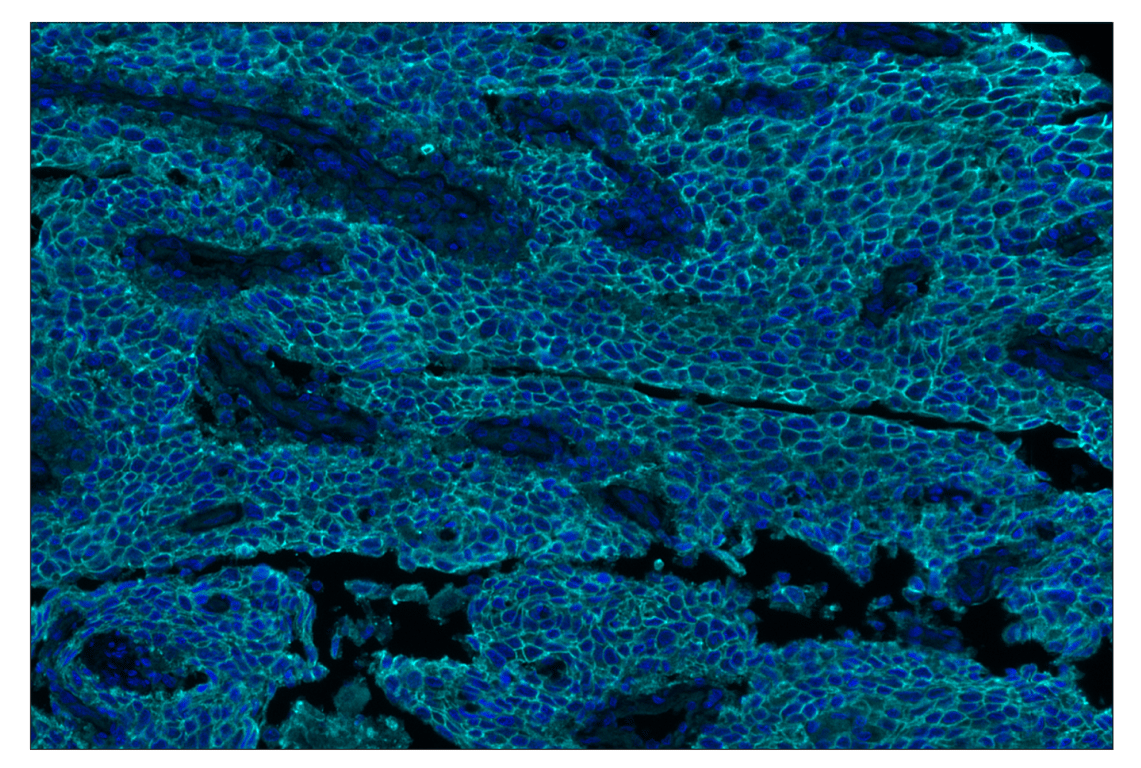

SignalStar™ multiplex immunohistochemical analysis of paraffin-embedded human squamous cell carcinoma of the cervix using TACSTD2/TROP2 (F4W4J) & CO-0150-750 SignalStar™ Oligo-Antibody Pair #64488 (cyan) and DAPI #4083 (blue). All fluorophores have been assigned a pseudocolor, as indicated. Staining was performed on the BOND RX autostainer by Leica Biosystems.

Immunohistochemistry Image 2: TACSTD2/TROP2 (F4W4J) & CO-0150-488 SignalStar<sup>™</sup> Oligo-Antibody Pair